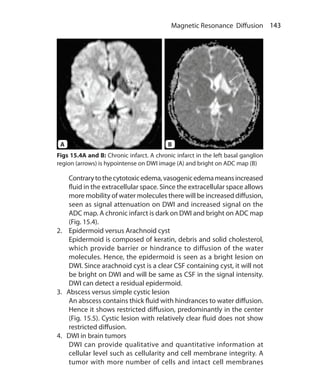

Figs 2.7A and B: T2-weighted image. (A)Tissue B has shortT2 that results into

early loss of magnitude of TM and reduction in signal. At short TE, there is no

significant difference between magnitude of TM of A and B. At long TE, signal

difference between A and B is more because tissue B will lose most of its signal

while tissue A will still have good signal. Since the image contrast is because of

differences inT2 of tissues, it isT2-weighted image. (B)T2-weighted axial image

of brain: CSF is bright; white matter is darker than gray matter